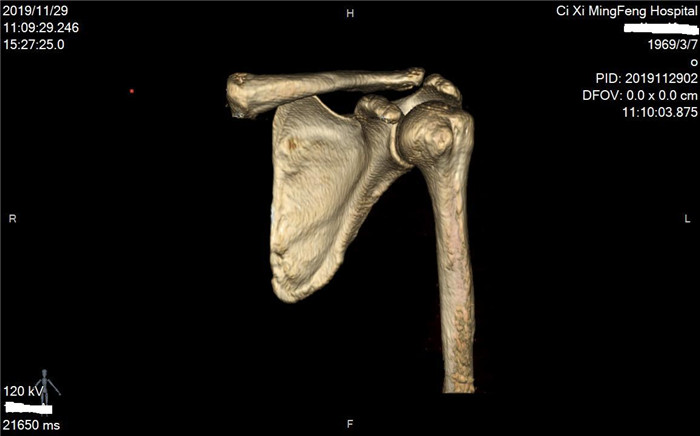

明峰CT搭載了領(lǐng)先的硬件技術(shù)平臺及系統(tǒng),強大的掃描能力可滿足臨床的各種要求,呈現(xiàn)更極致的細節(jié),為各臨床科室提供高品質(zhì)的圖像。薄層掃描,消除部分容積效應,提高各向同性。配合高分辨率算法,有助于細微結(jié)構(gòu)和形態(tài)學顯示。